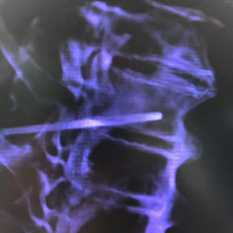

• Позвоночник:

о Утолщение трабекул позвоночника, малочисленность горизонтальных трабекул («полосатый» вид)

о Компрессионные переломы

о Околопозвоночные объемные образования, обусловленные внекостномозговым кроветворением

(Справа) КТ, корональный срез: у этого же пациента определяется как спленомегалия, так и утолщение трабекул. (Слева) КТ, аксиальный срез: у этого же пациента определяются оставшиеся трабекулы тела позвонка в виде рисунка в «мелкий горошек». Околопозвоночные мягкотканные объемные образования соответствуют внекостномозговым очагам кроветворения, также характерным для талассемии.

(Справа) Рентгенография в ПЗ проекции: у этого же пациента определяется крайне выраженная остеопения осевого скелета и обусловленные ей компрессионные переломы позвоночника.

(Слева) Рентгенография в боковой проекции: определяется утолщение вертикальных трабекул и немногочисленность горизонтальных трабекул, обусловливающих характерную для талассемии полосатую картину Обратите внимание на расширение костномозговой полости.

(Справа) Рентгенография в ПЗ проекции: у ребенка с талассемией определяется расширение костномозговой полости с утолщенными трабекулами и истончением кортикальной пластинки. (Слева) Рентгенография в боковой проекции: определяется выраженное расширение костей свода черепа и картина по типу «волос дыбом». Обратите внимание на увеличение вдавлений от сосудов костей черепа.